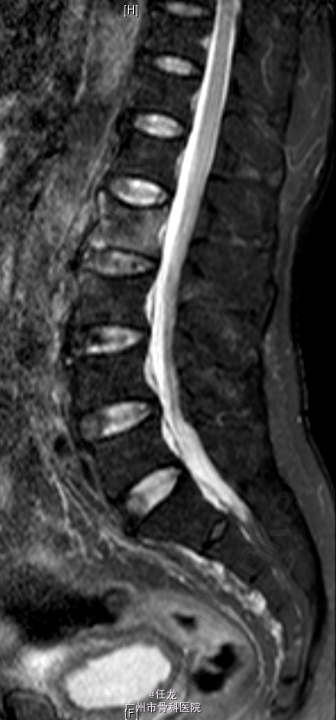

主诉:前列腺癌术后8年,反复腰痛半年,加重2周。 病史:患者8年前曾诊断为前列腺癌,并在外院行手术治疗,并多次放疗,一般坚持门诊复查。半年前出现腰部疼痛,为持续性疼痛,休息后无缓解,无双下肢麻木疼痛。最近两周加重明显,影响睡眠。遂至门诊就诊,门诊MRI考虑:前列腺癌腰椎转,故收入院作进一步诊治,患者一般情况较差。

查体:L2-L4棘突及棘旁轻度叩压痛。四肢感觉、肌力及肌张力正常。双侧坐骨神经出口处无轻压痛。双侧直腿抬高试验(-),双侧股神经牵拉试验(-)。双侧膝反射及踝反射未引出,双侧踝阵挛阴性。双侧Babinski 征及Oppenheim 征(-)。 辅助检查:PSA:73.22ng/ml ↑。腰椎影像学检查如下。

诊断:1. 前列腺癌腰椎转移 2.前列腺癌切除术后 处理:入院后完善相关检查,术前给予对症治疗,科里术前讨论决定:拟行手术:L2-4经皮穿刺活检+术中放疗+椎体成形术。